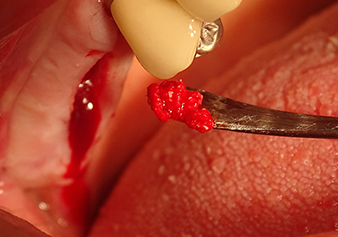

Затем, с помощью инструмента I2A (диаметр 2,0 мм), дно пазухи перфорировалось периодически и в минимально возможном диапазоне. Этот специфический пьезохирургический метод гарантирует, что мембрана Шнейдера не будет повреждена. При использовании Z25P, мембрана уже была слегка приподнята охлаждающей жидкостью, подаваемой через наконечник инструмента (рис. 3). Во избежание высокого давления в ложе имплантата, количество охлаждающей жидкости составляло не более 50%.